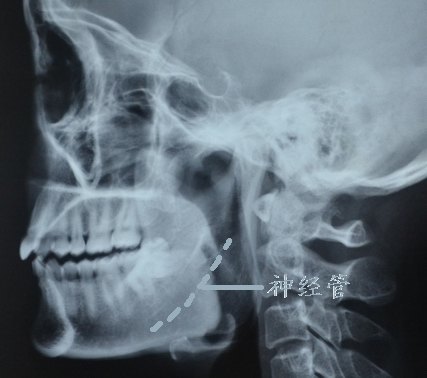

磨骨 颧弓颧骨内窥镜提升下颌角皮质截骨

下颌升支倒l型截骨术,c型截骨术

下颌角肥大的不同的截骨手术方式